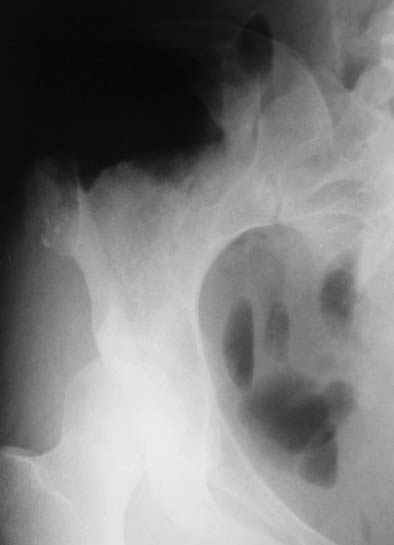

Остеохондрома подвздошной кости

еще фото

Руслан Шарафиев 18 Май 2005, 11:22

В данный момент была выполнена биопсия новообразования. Материал в работе.